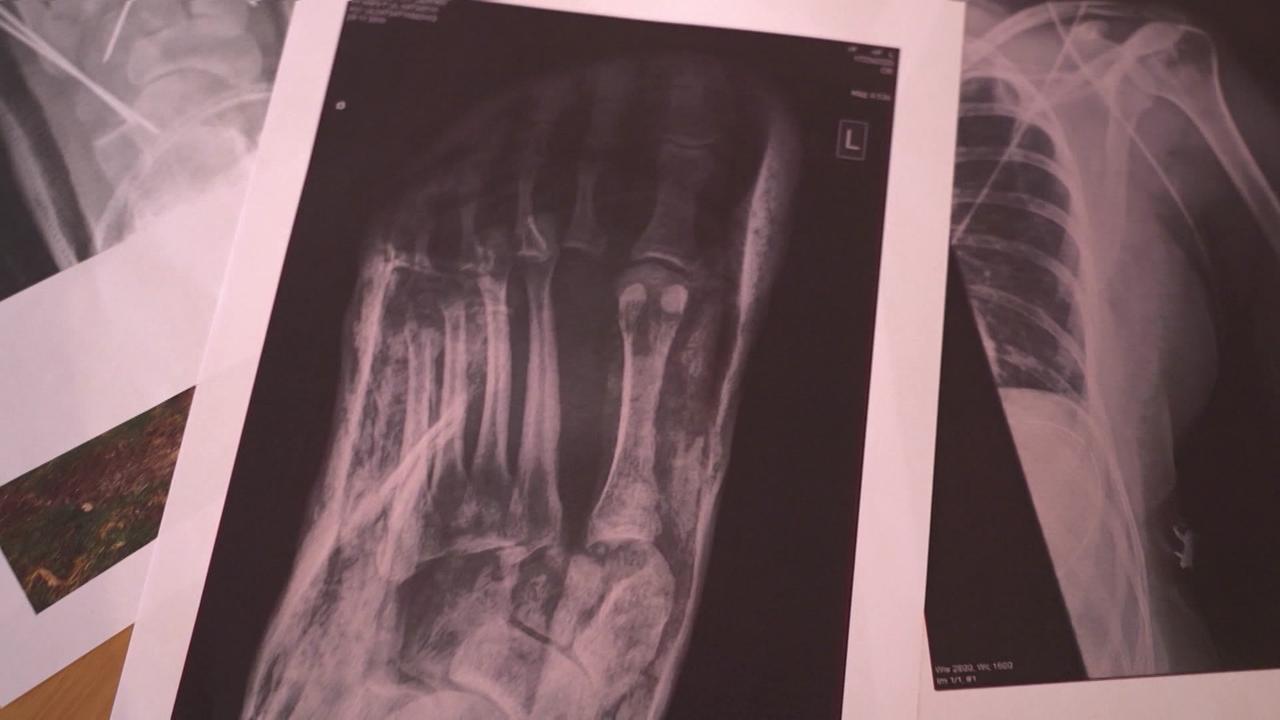

Unverschuldet verletzt - Wann zahlt die Versicherung des schuldigen Lenkers?

Frau M. wurde bei einem Autounfall, an dem sie keine Schuld hatte, schwer verletzt. Sie leidet bis heute an den Folgen dieses Frontalzusammenstoßes, der ihr Leben nachhaltig verändert hat. Sie ist arbeitsunfähig und verzweifelt. Obwohl die Haftpflichtversicherung des Unfallgegners auch für alle unfallkausalen Spätfolgen einstehen muss, gibt es regelmäßig Konflikte darüber, welche Schmerzen, Therapien oder Behandlungen vom Unfall herrühren. Gibt es jetzt nach 14 Jahren und mehr als ein Dutzend Verhandlungen eine Lösung?